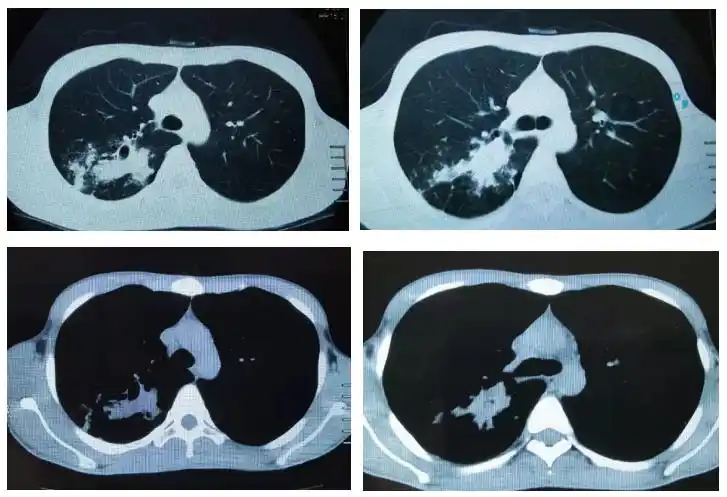

典型急性粟粒性肺结核

从ct上判断肺结核传染性的三种征象

肺结核之烟花征——黄勇老师经典病例分享